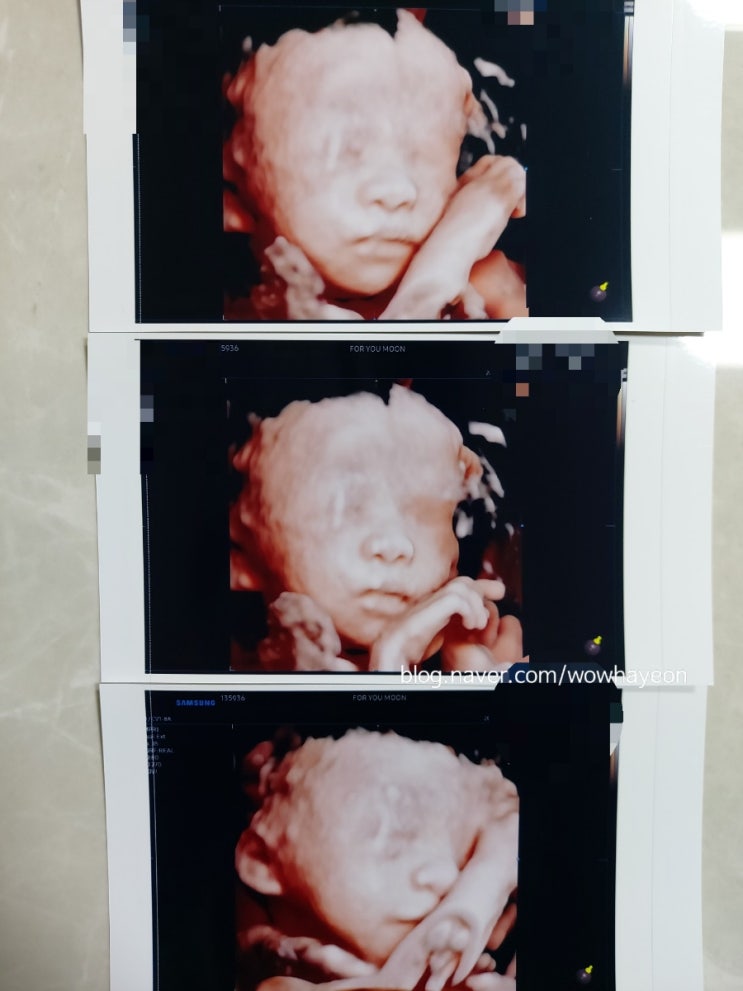

27주, 아기얼굴 입체초음파(감동)

울 아들도 초상권이 있겠지만 엄마 맘대로 블로그에 기록한다❤ 아기얼굴 입체초음파를 본 오늘이 임신기간...